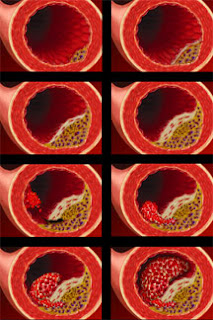

A aterosclerose é uma doença crônica-degenerativa

que leva à obstrução das artérias

(vasos que levam o sangue para os tecidos) pelo acúmulo

de lípides (principalmente colesterol) em suas paredes.

A aterosclerose é causada pelo acúmulo de lípides

(gorduras) nas artérias, que podem ser fabricados pelo

próprio organismo ou adquiridos através dos

alimentos. Ela começa quando monócitos (um tipo

de leucócito mononuclear) migram da corrente sangüínea

e depositam-se nas paredes arteriais e passam a acumular

gorduras, principalmente colesterol, formando as placas

ateroscleróticas ou ateromas.

As artérias afetadas pela aterosclerose perdem

elasticidade e, à medida que essas placas de gordura

crescem, as artérias estreitam-se.

Eventualmente essas placas podem se romper, havendo o

contato das substâncias do interior da placa com o

sangue, o que produz a imediata coagulação do

sangue e, como conseqüência, a obstrução

total e súbita do vaso, o que leva ao infarto do miocárdio.